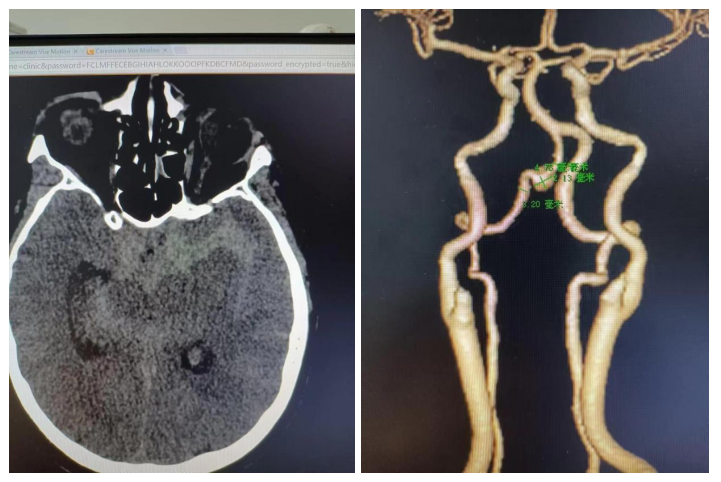

50岁的女性患者突然晕倒在地,右侧肢体活动受限,突然失语,拨打120经急诊紧急入院。急查颅脑CT、头颈CTA。CTA提示颅内多发动脉瘤。双侧大脑中动脉及右侧椎动脉各有一个动脉瘤,共有三枚动脉瘤。并进行了相关对症处理。脑外科田德洲主任及董永军副主任医师参与急会诊。经检查认为,患者颅内动脉瘤破裂伴有蛛网膜下腔出血,考虑患者有高血压病史10年,最高血压190/120mmHg,如果不及时处理,后果不堪设想。脑外科治疗团队立即启动MDT线上会诊,邀请北医三院韩金涛教授会诊,决定为患者进行多发动脉瘤同期介入栓塞治疗。

为避免患者病情进一步恶化,把握黄金救治时间,与患者家属沟通征得同意后,紧急制定了微创介入手术治疗方案,争分夺秒挽救生命。经过充分的术前准备,在麻醉手术科团队全力配合下,脑外科团队为患者进行了“全脑血管造影术+左侧大脑中动脉动脉瘤介入栓塞+右侧椎动脉V4段动脉瘤介入栓塞术。”手术顺利,术后转入ICU 进一步治疗,术后一周患者状况恢复良好,现已顺利出院。